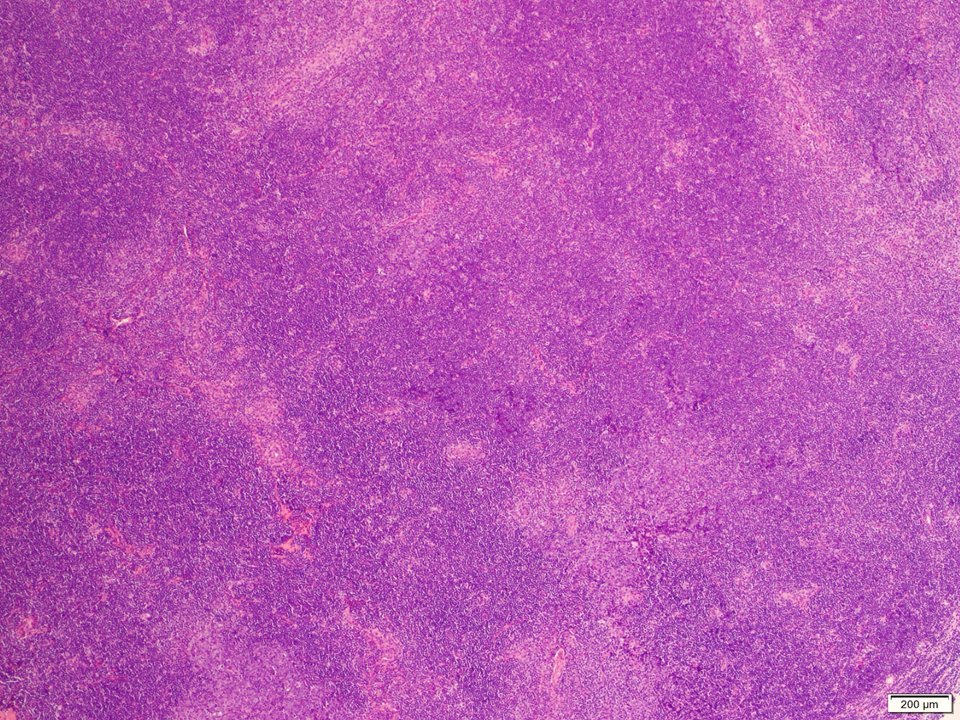

(1/3) Mutlifocal DLBCL arising in a background of low grade follicular lymphoma, with a peculiar architecture #hemepath #LJMFridayUnknowns #VirtualHemepathMDA #lymsm #endcancer